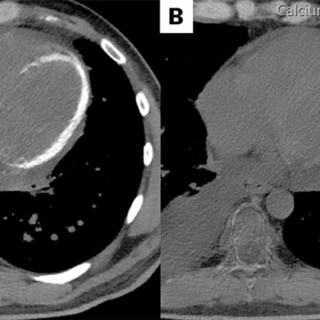

CT-bildene er fra en undersøkelse med opptak uten intravenøs kontrast. Bildet til venstre viser høy attenuasjon i myokard i venstre ventrikkel, og i mindre grad i høyre ventrikkel. Attenuasjonen er tilnærmet lik skjelett i bildet, og tettheten kan passe med forkalkninger. Opptaket er gjort på en spektral-CT, som har økt mulighet for å differensiere mellom ulike vevstyper. Maskinen utnytter de ulike energinivåene i røntgenstrålen, og den kan skille mellom grunnstoffer som jod og kalk utfra absorpsjonsnivået, da begge gir høy attenuasjon. Kalksuppresjon, vist på bildet til høyre (B), bekrefter...